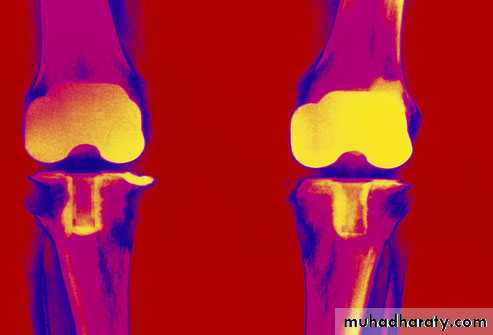

Radiological findings

Radiographic changes typical of RA